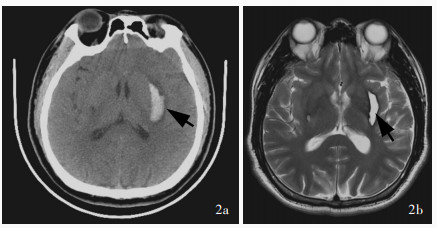

Sun GC , Chen XL , Hou YZ , Yu XG , Ma XD , Liu G , Liu L , Zhang JS , Tang H , Zhu RY , Zhou DB , Xu BN . Image - guided endoscopic surgery for spontaneous supratentorial intracerebral hematoma. J Neurosurg, 2017, 127: 537- 542.

doi: 10.3171/2016.7.JNS16932